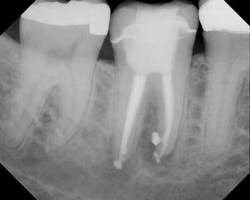

Postop